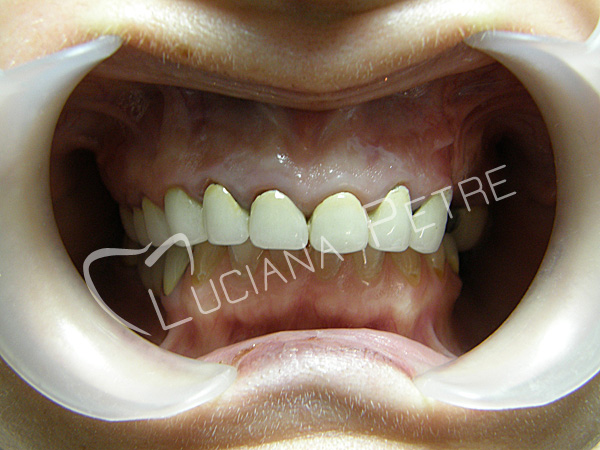

Estetica rezolvata cu coroane din

ceramica pe zirconiu